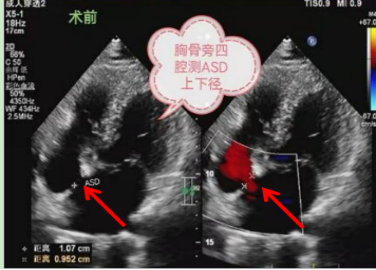

术前超声心动图